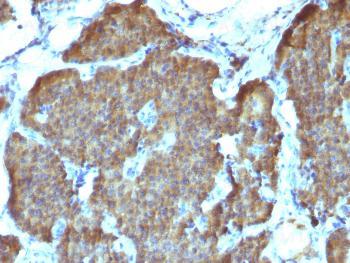

Fig. 1: Formalin-fixed, paraffin-embedded human Pheochromocytoma stained with NSE gamma Monoclonal Antibody (SPM347).

Recognizes a protein of about 50kDa, which is identified as gamma-enolase. Three isoenzymes of enolases are identified, alpha, beta and gamma. Alpha-isoform is expressed in most tissues, whereas beta-form is expressed predominantly in muscle tissue whereas gamma-enolase is found only in nervous tissue. These isoforms exist as both homodimers and heterodimers, and they play a role in converting phosphoglyceric acid to phosphenolpyruvic acid in the glycolytic pathway. NSE-gamma is a useful marker to identify peripheral nerves and tumors of neuro-endocrine origins, such as pheochromocytomas.It it be usually employed in combination with other markers such as Synaptophysin,Chromogranin A, and Neurofilament.